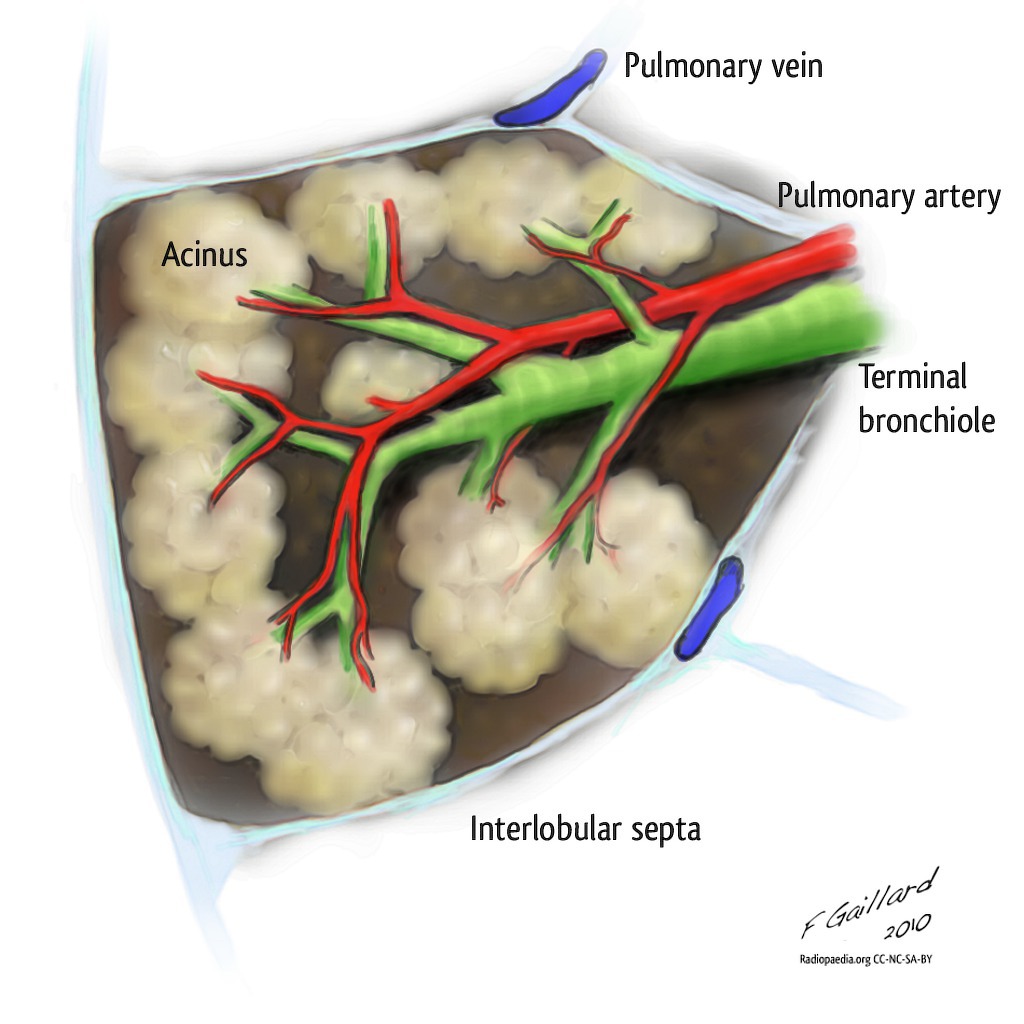

The conducting zone and acinus

Bronchi undergo an average of 23 divisions. The first 16–17 generations form the conducting zone - anatomical dead space, no gas exchange. Beyond a terminal bronchiole lies the acinus - the gas-exchanging unit - comprising respiratory bronchioles, alveolar ducts, and alveoli.

Bronchopulmonary segments

A bronchopulmonary segment (BPS) is an anatomical unit of lung supplied by a specific tertiary (segmental) bronchus with an accompanying segmental artery. The general pattern is 10 segments on the right and 8 segments on the left - LB1/2 and LB7/8 are typically fused on the left.

Pyramidal in shape - apex towards the root of the lung, base towards the surface. Each segment has its own arterial supply and segmental bronchus. Pulmonary veins run in intersegmental planes, not alongside bronchi - forming the surgical plane between adjacent segments.

Each BPS has no communication with adjacent segments - making segmentectomy possible without damaging neighbours. Intersegmental planes are marked by intersegmental veins, which serve as the surgical guide. There is little bleeding or air leak after segmentectomy if the intersegmental plane is correctly developed.